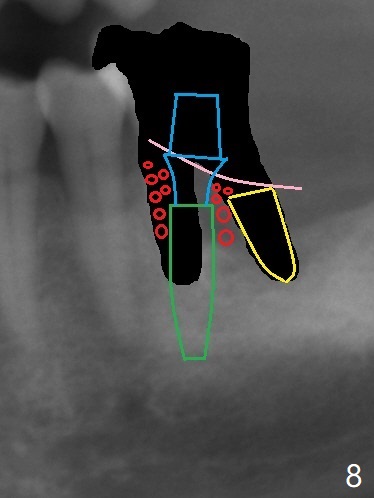

After tooth extraction (Fig.4), a medium-sized implant (4.5 mm, Fig.5 green) will be placed in the mesial socket, but the coronal end of the long axis of the implant (white line) will be in the middle of the socket for future restoration. The gingival margin of the socket is also uneven (Fig.6 pink). Before placement of the final abutment (Fig.7 blue), pack allograft (red circles) over the exposed implant surface until the platform of the implant. After placement of Osteogen plug in the distal socket (Fig.8 yellow), more of allograft is placed coronally. An immediate provisional (Fig.9 white) is to be fabricated to keep the graft in place. If the socket is deemed to be unsuitable for immediate implant, place PRF membrane(s) distoocclusally (Fig.10 purple), followed by collagen membrane and suturing.